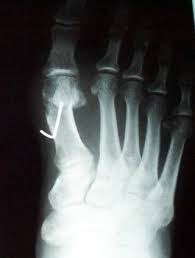

Rx post operatoria: molto soddisfacente!